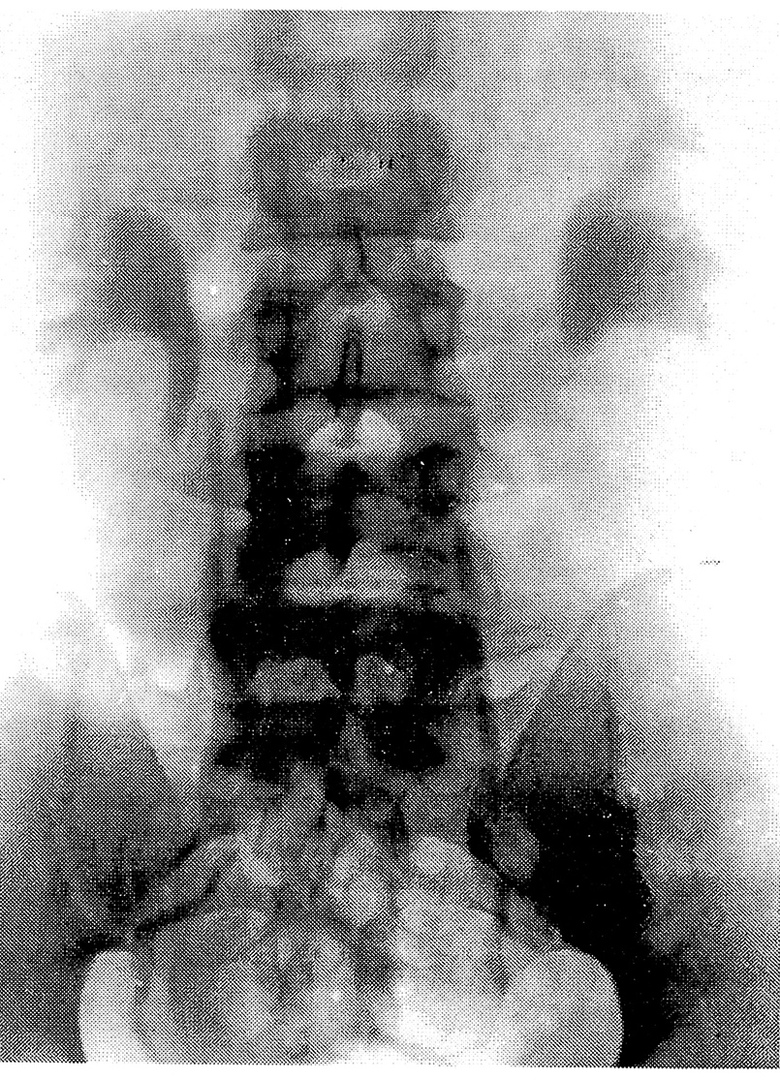

Рис. 2. Внутривенная экскреторная урография больной Н., 34 лет, в клиностазе: двусторонний нефроптоз, гидронефротическая трансформация, коленообразные перегибы мочеточников. Нефроптоз III степени в ортостазе

Кроме того, мы вычисляли относительное сужение и удлинение почечной артерии (рис.3). В норме ПУУ равен 110— 130°. В ортостазе он уменьшается на 10— 20°. При нефроптозе он становится острым в зависимости от степени смещения. Но величина этого угла не всегда соответствует степени смещения почки: при небольшом смещении вниз возможна более выраженная ее ротация, и наоборот. По разнице ПУУ на ВЭУ в клиностазе и ортостазе можно вычислить поворот почки вокруг продольной оси. Для вычисления поворота почки вокруг поперечной оси и определения степени нефроптоза, по данным ВЭУ, определяли длинник почки в положении больного лежа и стоя. По разнице длинни- ков почек вычисляли искомый угол по формуле (1/2R : 1/2 R1) = cosа. Относительное сужение почечной артерии при нефроптозе, по данным ВЭУ, определяют следующим образом: на урограмме в клиностазе по левому краю остистых отростков позвоночника проводят вертикальную линию (при нефроптозе справа — соответствующую правому краю аорты). Место отхождения почечной артерии соответствует пересечению горизонтали от шейки верхней малой чашечки к краю аорты, h — длина почечной артерии в клиностазе и h1 — в ортостазе. Сужение почечной артерии вычисляли по формуле: V= Пr2h (лежа); Ѵ= Пг21h1; r2h= г1 2h1. Относительное сужение почечной артерии r1=√h/h1 х 100г, где (в %) г/г = √h/h. В настоящее время нарушение кровообращения, диаметры почечной артерии и вены можно определить используя УЗИ с ЦДК.При патологической подвижности почка не только смещается в каудальном направлении, но и поворачивается вокруг продольной и фронтальной (поперечной) осей. Как известно, в норме в ортостазе ротация почки не превышает 19°. Формальная степень смещения не полностью отражает характер и тяжесть нарушения механизма фиксации почек. Важно установить ортостатические нарушения функции почек (нарушение кровообращения, уродинамики, функциональные расстройства почек). Ротацию почек в ортостазе мы определяли по А.И. Радавичус, Ч.А. Синкевичус [4] (рис.1, 2).